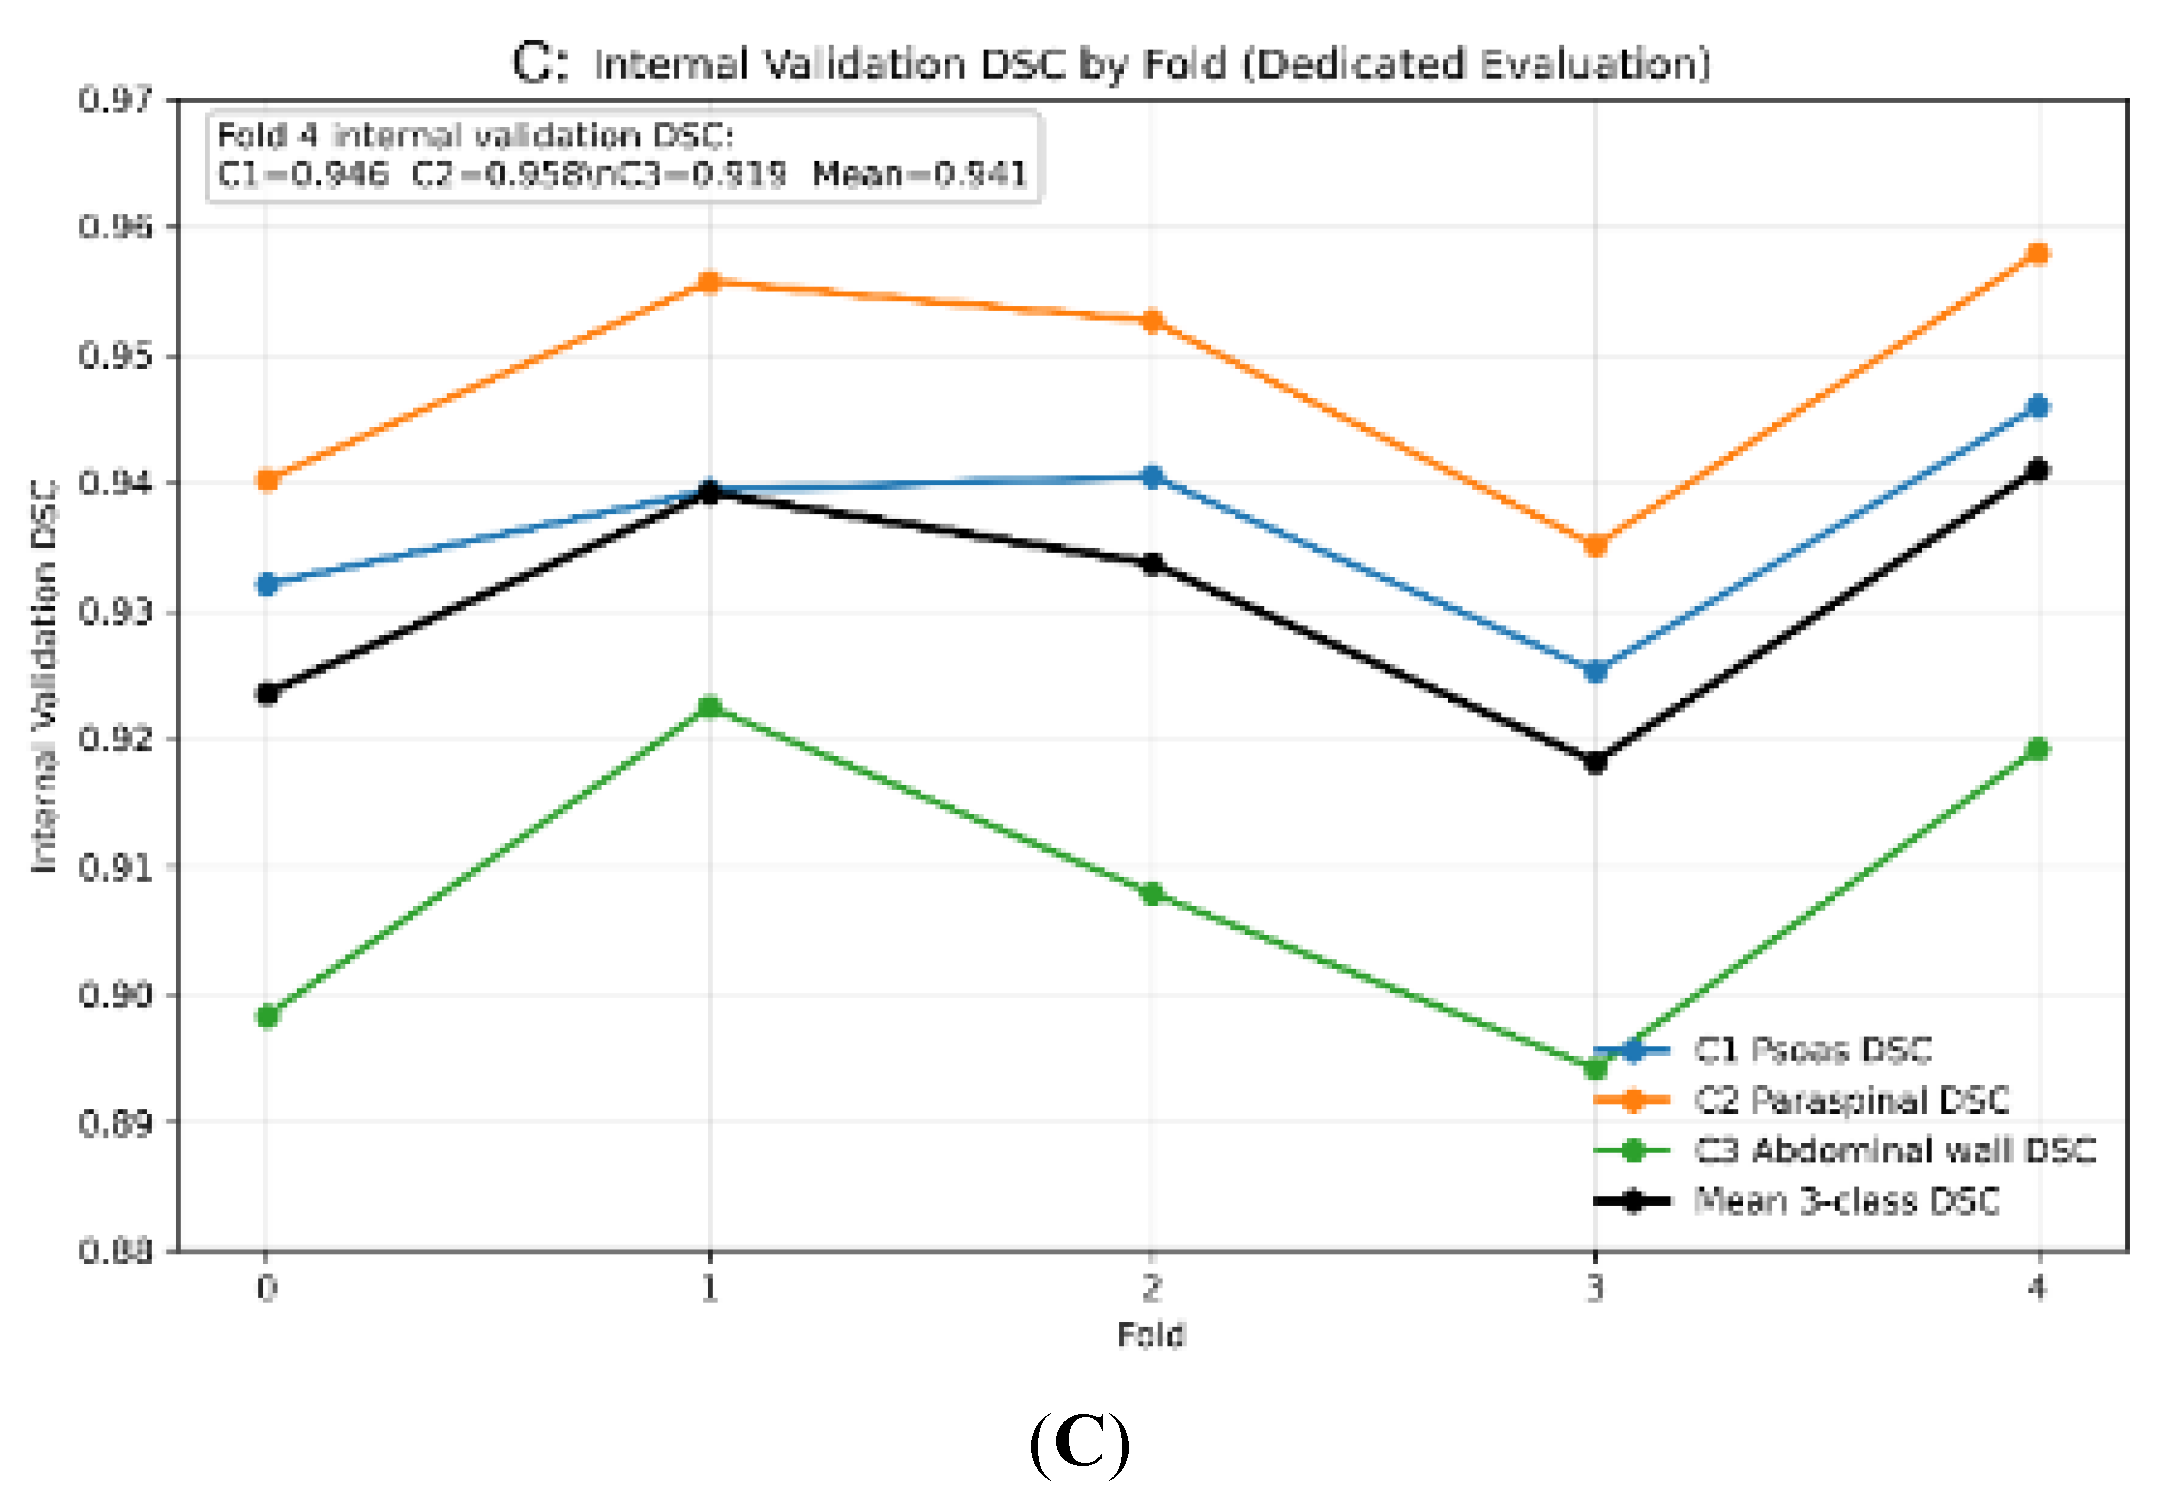

3.1. Internal Cross-Validation Performance

| Fold | Psoas | Paraspinal | Abdominal wall | Mean DSC |

|---|---|---|---|---|

| 0 | 0.932 | 0.940 | 0.898 | 0.924 |

| 1 | 0.939 | 0.956 | 0.923 | 0.939 |

| 2 | 0.941 | 0.952 | 0.908 | 0.934 |

| 3 | 0.925 | 0.935 | 0.894 | 0.918 |

| 4 | 0.946 | 0.958 | 0.919 | 0.941 |

| Mean | 0.937 | 0.948 | 0.908 | 0.931 ± 0.010 |